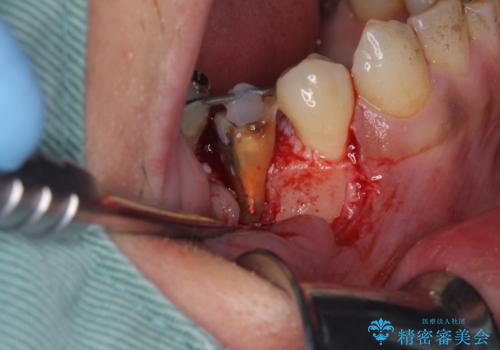

当初は根管治療を再度行うことで痛みが引くことを期待しましたが、該当歯の歯周ポケットが局所的に深くなっていることから、歯に穴が開けられているか破折している可能性が疑われました。

歯肉を開いたところ、周辺の歯槽骨は全て炎症で失われ、破折と同等の穴が開けられていることが分かったため、抜歯を行いフルジルコニアブリッジにて補綴することとしました。